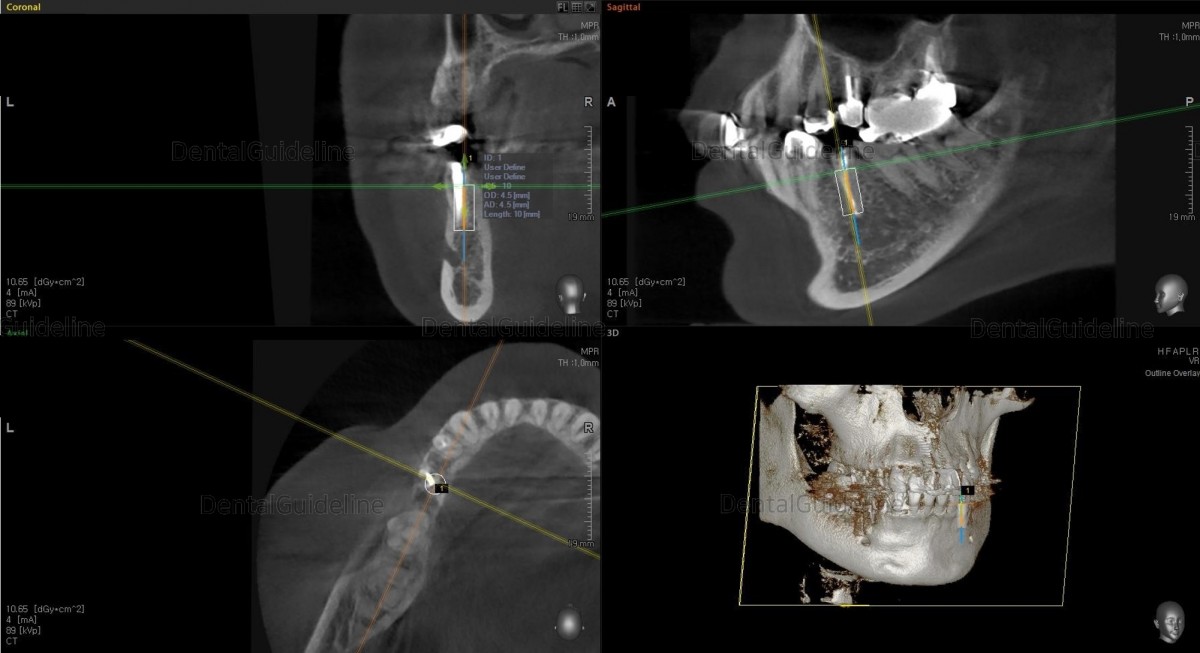

Simple simulation on the CBCT scan image.